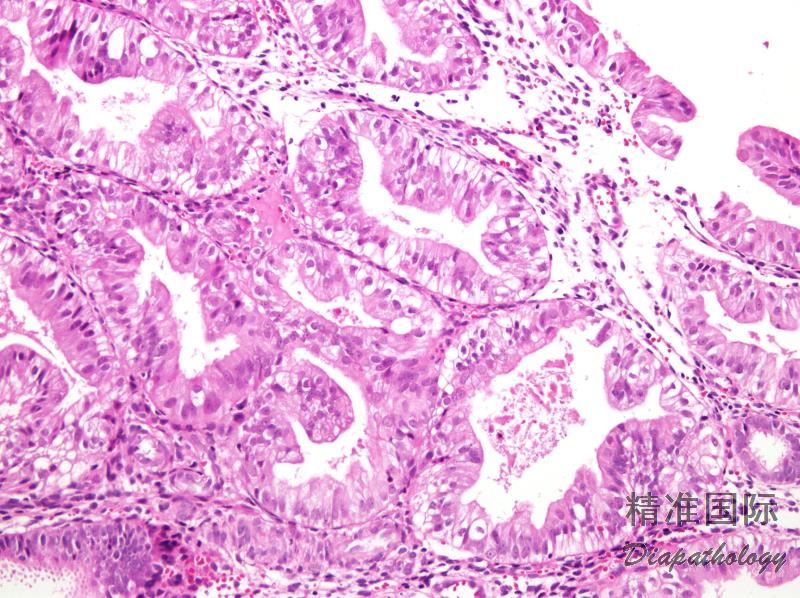

简单性非典型增生的腺体轮廓可呈轻度复杂性,可形成腺腔内簇状突起,但腺体之间有丰富间质,无“背靠背”现象;

复杂性非典型增生的腺体结构是高度复杂、形状不规则,并有“背靠背"密集现象。